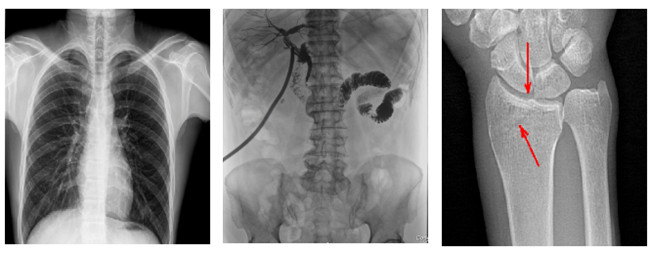

普利德多功能悬吊动态DR,搭载100μm高品质动态平板探测器,不仅满足常规的数字化X线全身摄影需求,同时还拥有数字摄影、数字透视、数字造影、全景拼接等多种功能,极大地拓展了X线检查在临床应用范围,为医院临床应用带来更多实用价值?;诎傥⑵桨宓母咔宄上?,图像清晰度与分辨率更高,可满足不同检查部位对细节成像的高品质要求,在胸腹部、脊柱等复杂骨骼和软组织的摄片上应用,更便于观察隐匿性病灶,精准识别疑难病症。

不同于静态DR拍摄隐匿性病灶时,由于组织重叠病灶难辨,耗费时间更长且易漏诊、误诊,普利德多功能悬吊动态DR可通过动态实时连续成像,对于重叠部位病灶或者易被遮挡的病灶进行多角度动态观察,毫秒级时间内实现动静态转换点片,快速、精准完成摄片。比如隐匿性肋骨骨折,可在透视下观察患者的呼、吸过程,避开重叠影像,快速点片,保证检查部位的病症不被遗漏,实现精准诊断。